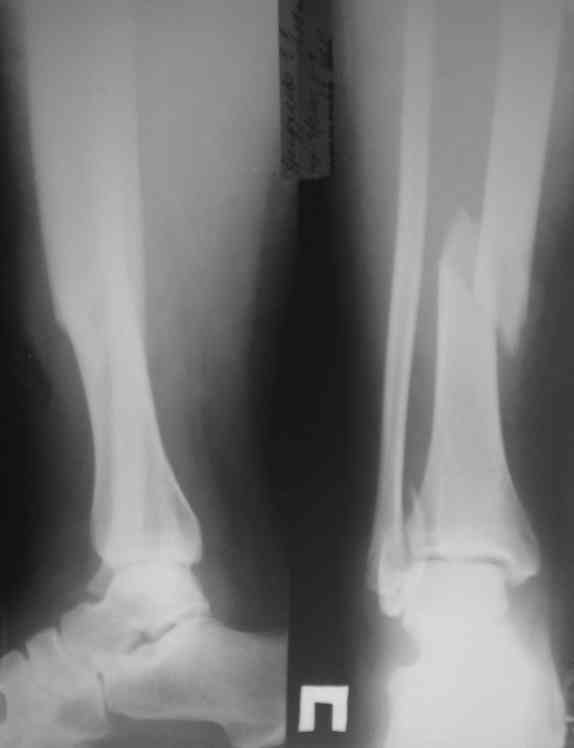

Представляю рентгенограмму перелома обеих костей голени, где определяется разрыв дистального межберцового синдесмоза.

Механизм травмы - подвернул ногу. На боковом снимке видно, что латеральная лодыжка поломана на уровне голеностопного сустава. Во время травмы, кроме воздействия крутящего момента на кости голени, происходило еще и стремительное движение тела больного вниз вместе с проксимальным отломком малоберцовой кости (сила земного притяжения), вследствие чего разрывается межкостная мембрана, передняя межберцовая связка (lig.tibiofibulare anterius), рудиментарная поперечная связка. На боковом снимке конец проксимального отломка ( в данном случае место прикрепления передней межберцовой связки) находится на уровне середины таранной кости. Соответсвенно, последняя разорвана. Смещение отломков костей голени по длине - около 2 см.

Соответственно, из составляющих ДМС осталась целой

лишь задняя межберцовая связка. Хирургу, который будет оперировать пациента, рекомендовано наложить шов передней межберцовой связки, и ввести позиционный винт выше ДМС.